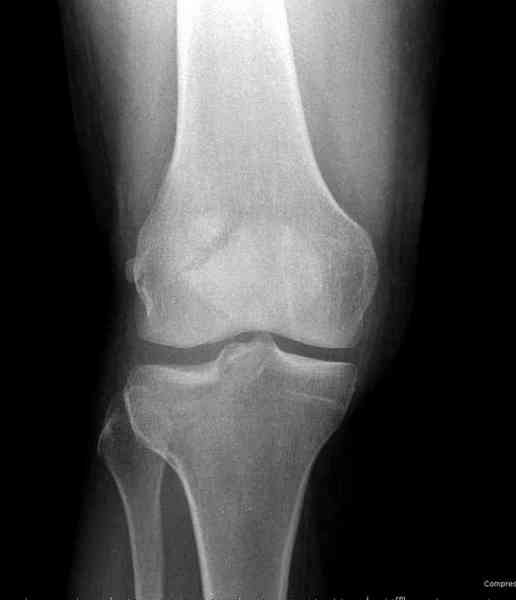

Как всегда прекрасная презентация. Совершенно согласен с необходимостью сохранять мениск и вообще согласен со всем, кроме одного. Фиксация должна проводиться после правильно выполненной репозиции. Главная цель репозиции - это восстановить высоту наружного мыщелка. В норме наружный мыщелок выше внутреннего на 4-5 мм на снимке в переднее заднем направлении АР.

Необходимость репозиции возникает при снижении высоты от 3 до 5 мм по разным источникам. По моему опыту 4 мм. Если не восстановить высоту мыщелка возникает вальгизация коленного сустава с относительным расслаблением передней крестообразной связки. При этом развивается нестабильность коленного сустава из-за недостаточности ПКС.

По этому если фрагмент большой есть необходимость репозиции дистального угла и фиксация пластинкой против соскальзывания ANTIGLIDING PLATE. Если перелом фрагментарный? то очень помогают описанные субхондральные шурупы RAFT, но

чтобы сохранить высоту суставной площадки шурупы одним концом должны опираться на пластинку а другим - на кортекс по внутренней стороне. Идеально сочетание ANTIGLIDING BUTRESS PLATE + RAFT SCREWS.